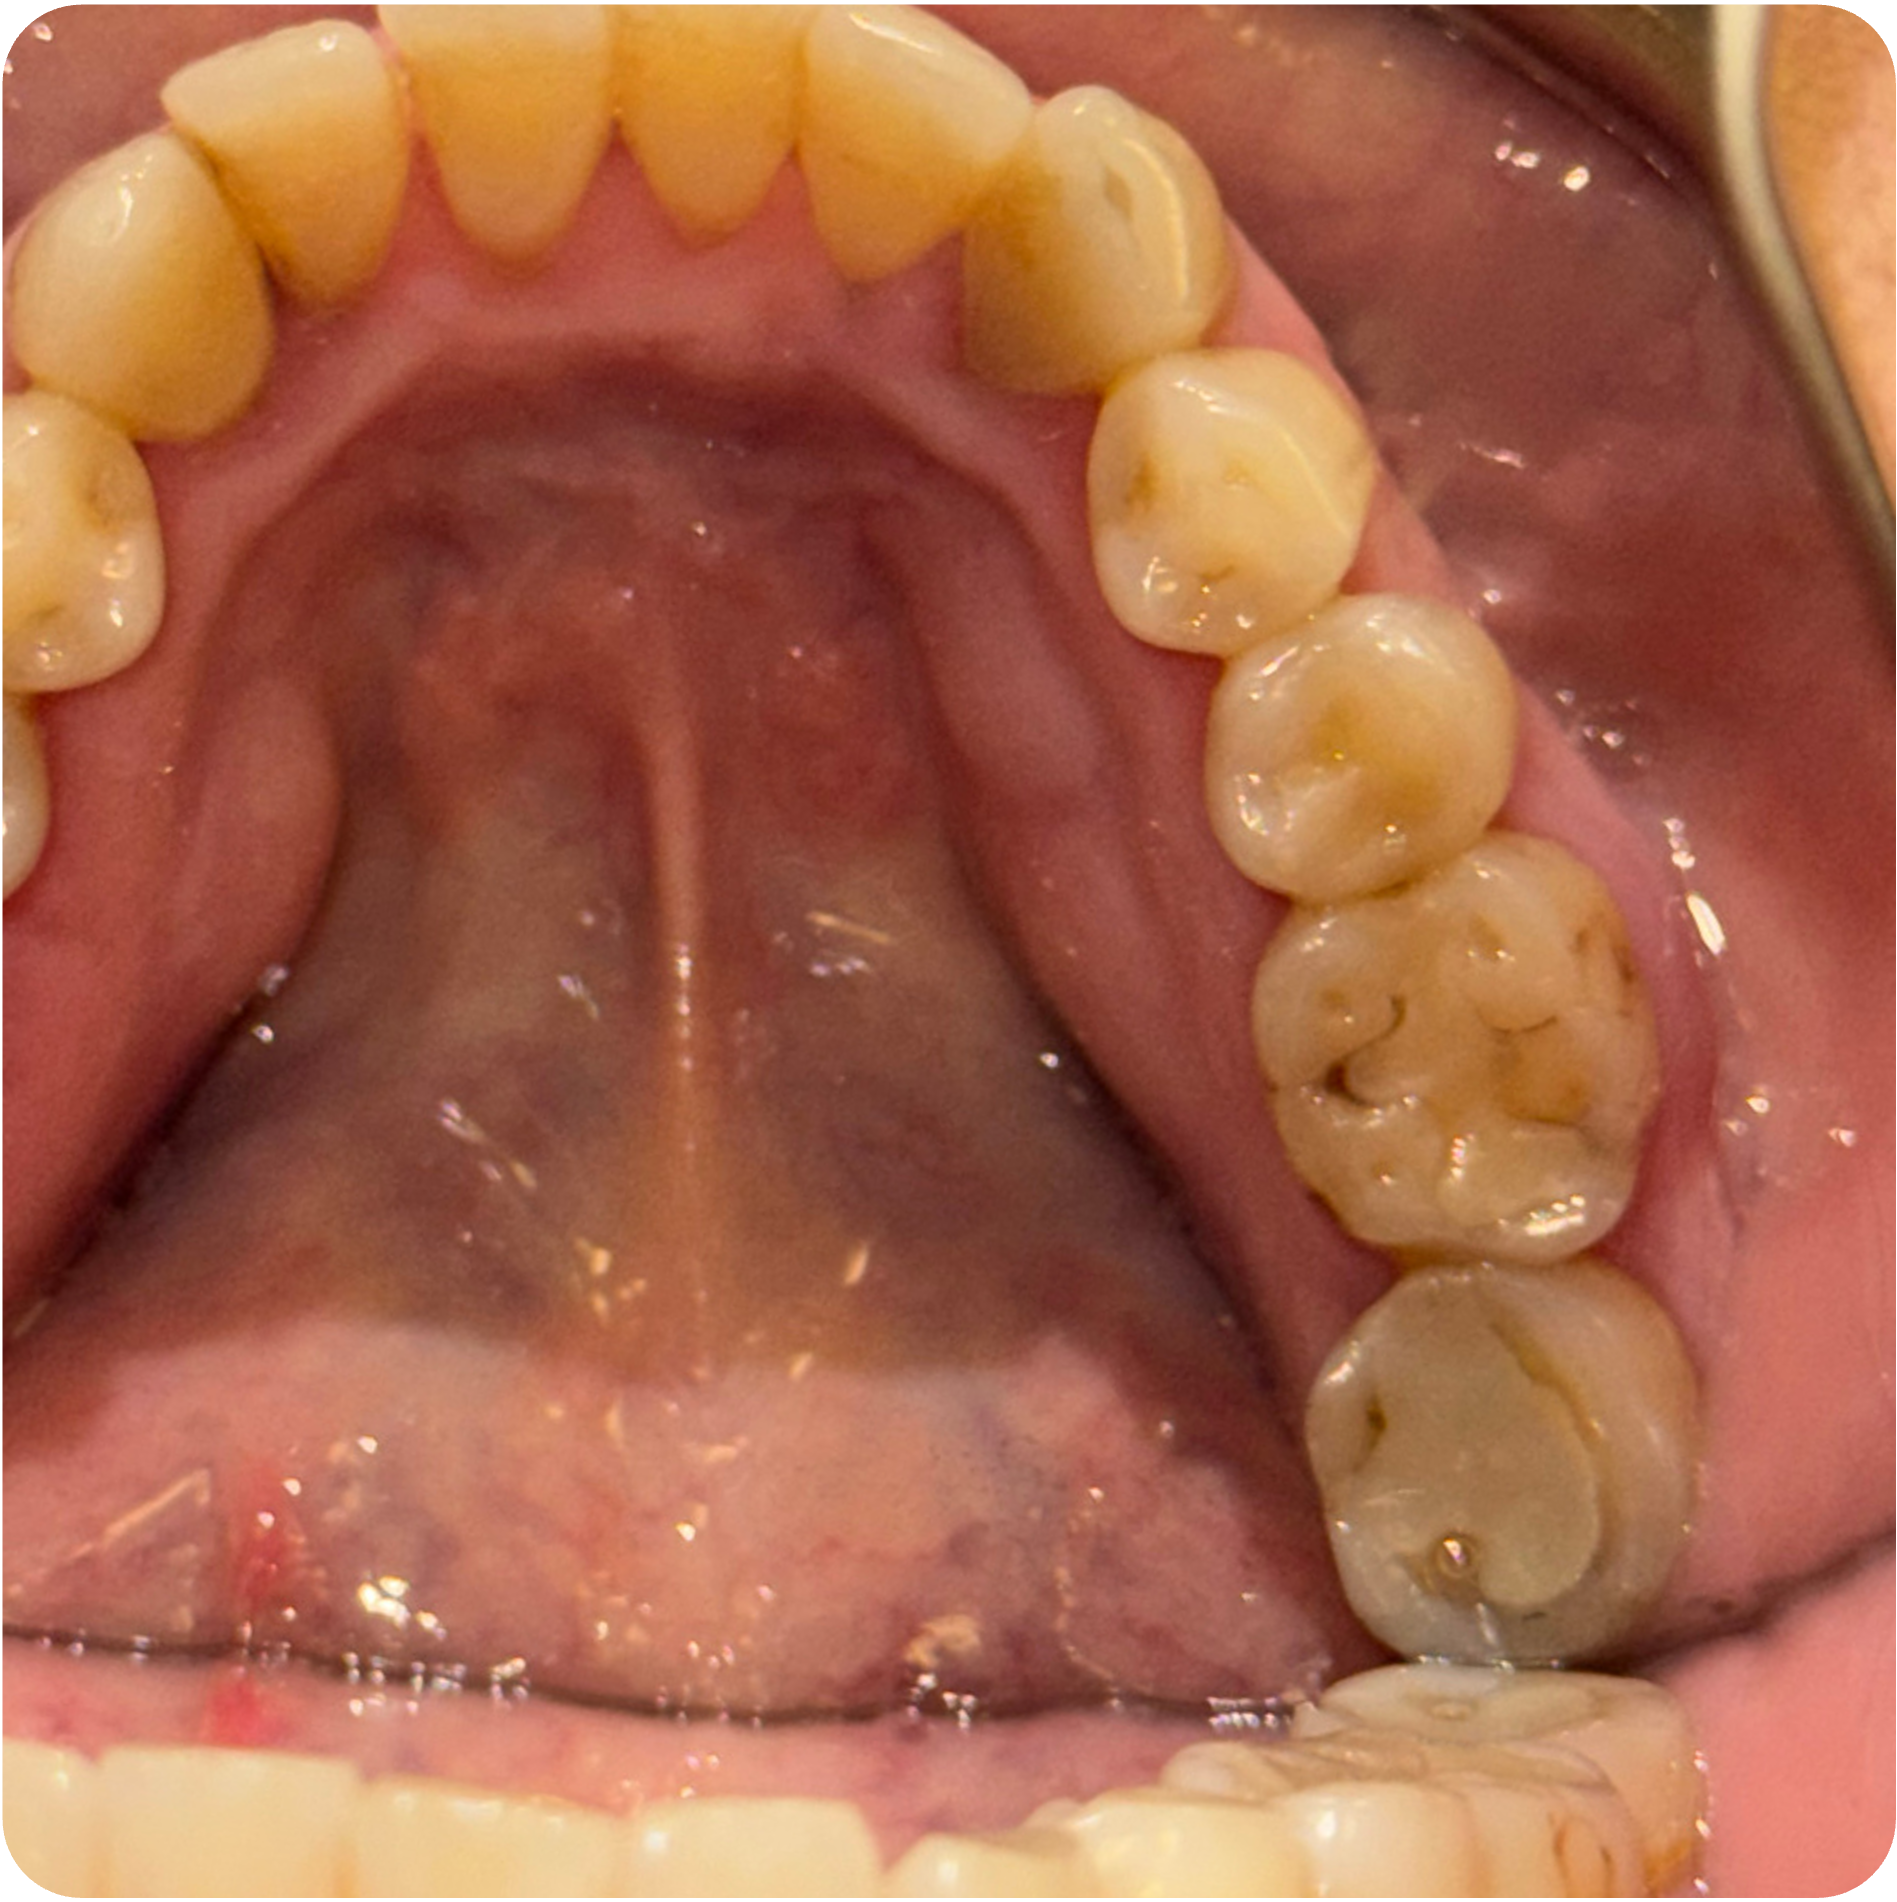

Visual Case Progression

All clinical images are shown at a consistent size for easy comparison.

Before & After (Groton Wellness Perio Protocol)